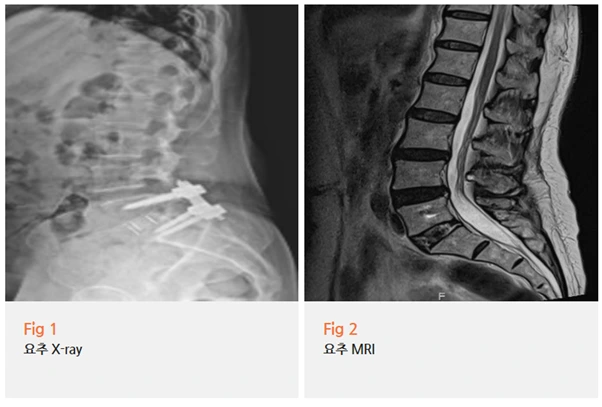

알고 보니 2024년에 요추 5번-천추 1번 척추 고정술을 받으셨던 분이었어요.

먼저 당일 MRI 검사를 진행했어요.

요추 퇴행성 디스크 소견과 근감소증 정도가 확인됐는데,

이걸로 지금 이 통증을 완전히 설명하기엔 부족했습니다.

영상에서 보이는 것과 실제 환자분이 느끼는 통증의 정도가

맞지 않는 경우가 임상에서 꽤 있거든요.